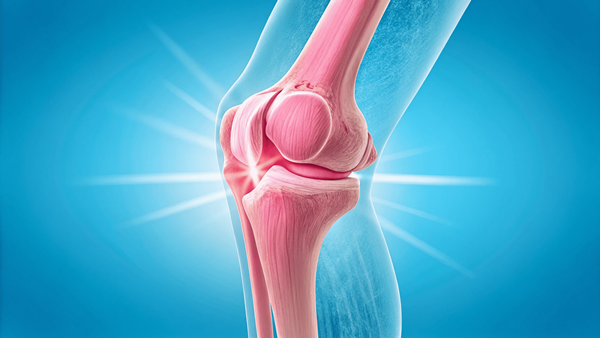

첫째, 연골을 재생시키고 손상을 줄이는 데 도움이 됩니다. 나이가 들수록 마모되는 연골은 스스로 회복되기 어려운데, 콘드로이친은 새로운 연골 세포의 생성을 도와 퇴행성 변화에 제동을 걸어줍니다.

둘째, 관절 사이를 부드럽게 만들어줘서 움직임이 편안해지죠. 관절액 생성을 도와주는 작용 덕분에 마찰이 줄어들고, 아침에 일어날 때 관절이 뻣뻣한 느낌도 덜하게 됩니다.

셋째, 관절염 같은 염증성 질환의 진행 속도를 늦춰줍니다. 만성염증은 관절 기능을 악화시키는 주범인데, 콘드로이친은 염증 매개물질의 활동을 조절해 관절을 진정시켜주는 작용이 있어요.

넷째, 통증을 줄이고 계단 오르내릴 때처럼 부하가 걸리는 순간에도 관절을 보호해주는 역할을 해요. 움직일 때 마디마디가 시큰거리는 분들이나, 하루 활동량이 많은 분들에게 체감 효과가 크다는 후기가 많습니다. 실제로 지인 중 한 분은 겨울철만 되면 손가락 관절이 욱신거렸는데, 콘드로이친을 꾸준히 복용한 뒤로는 장갑 없이도 장을 보러 다닌다고 해요. 그렇게 체감되는 효과들이 조금씩 쌓이면 일상이 훨씬 가벼워지죠.